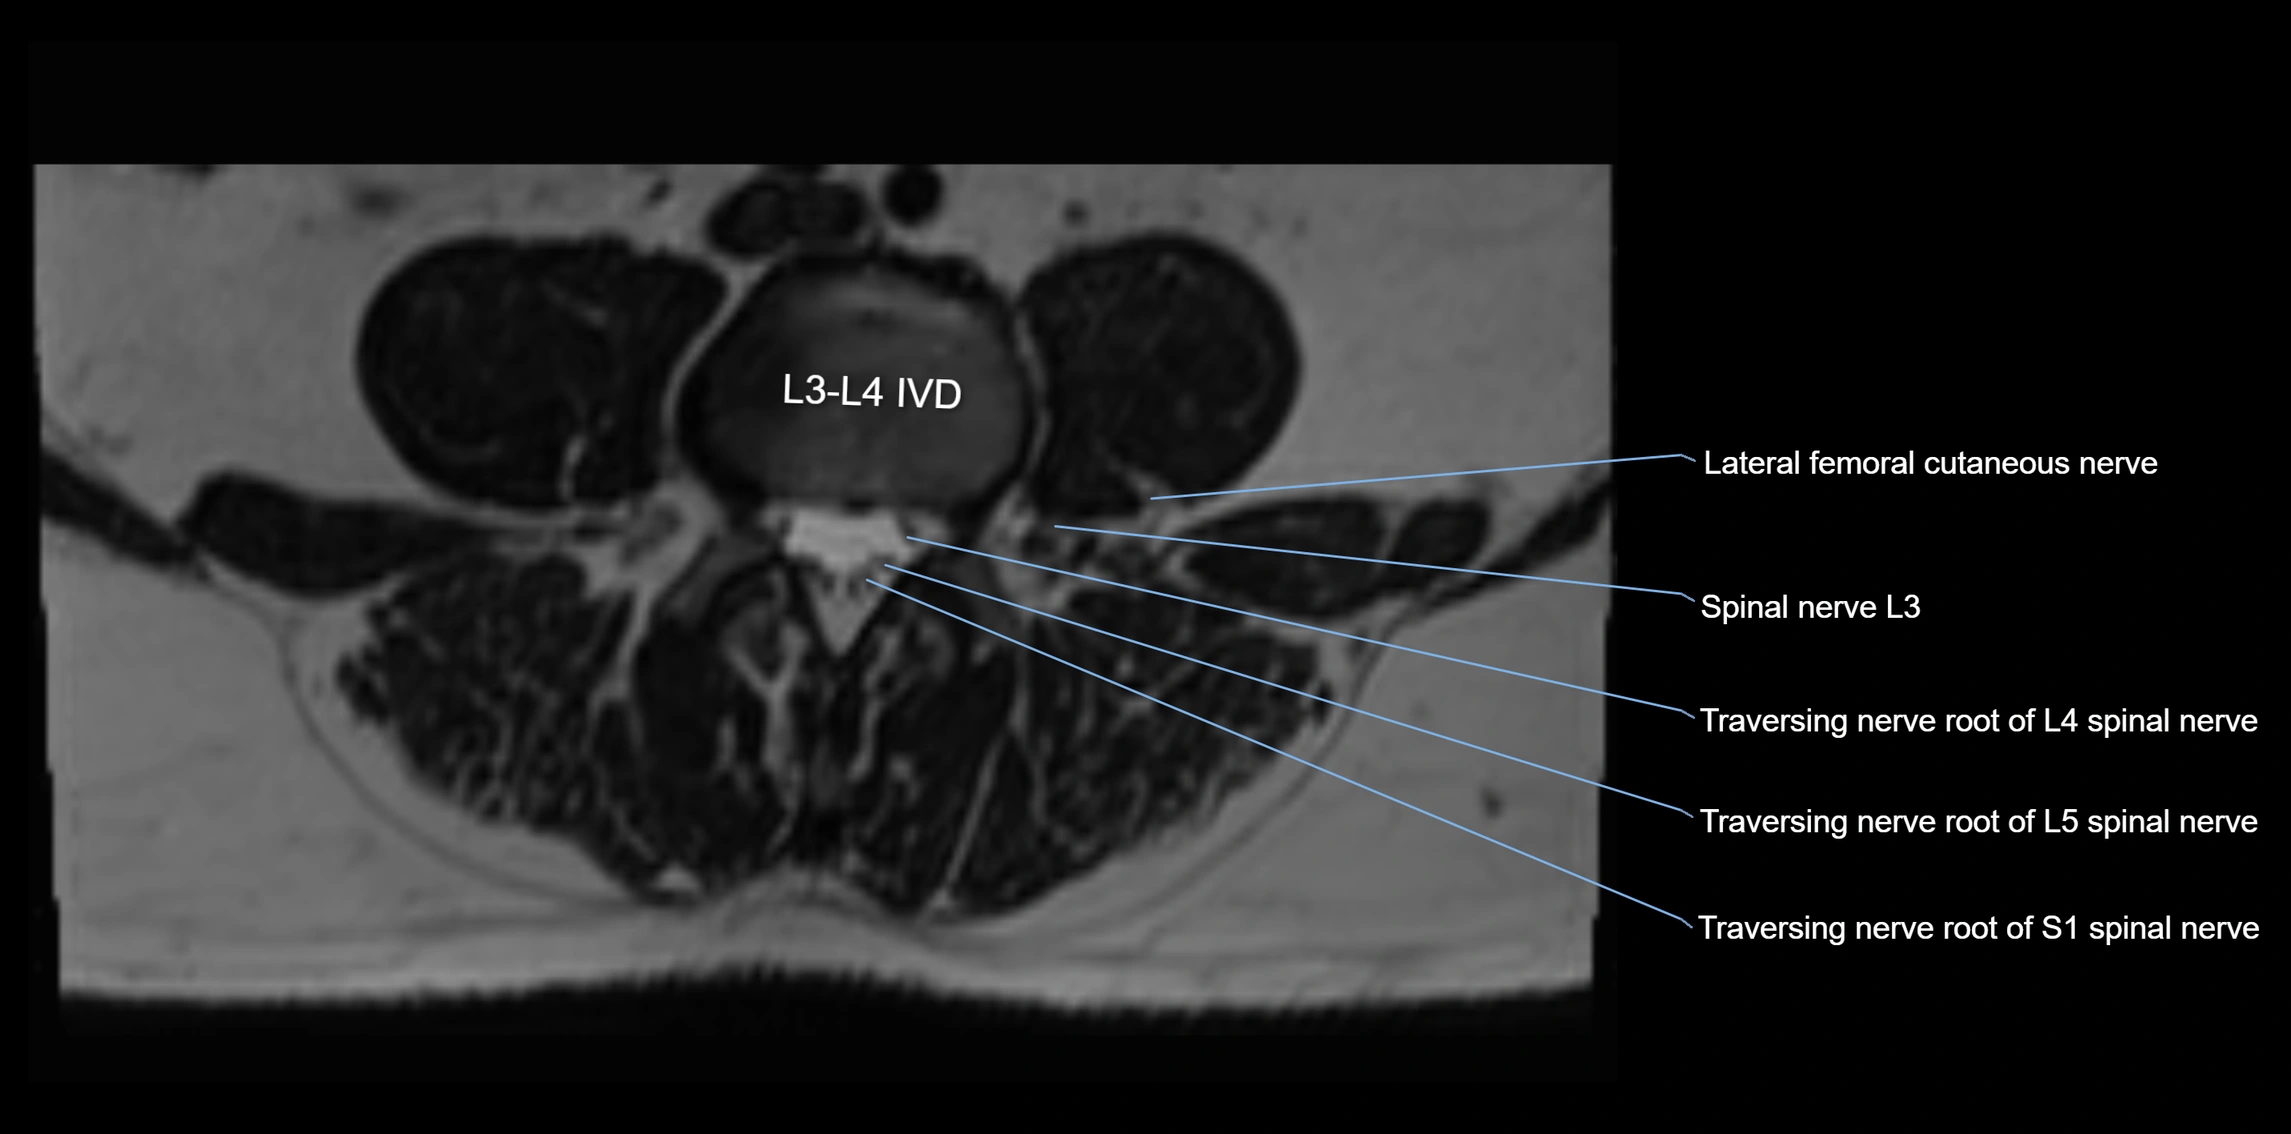

MRI image

image